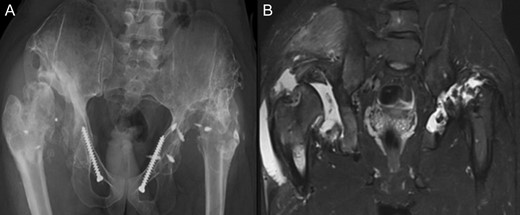

(A + B): (2008) (A) Hip reconstruction with open reduction, Tönnis triple pelvic osteotomy and shortening rotational varus osteotomy of the left femur demonstrating correct deep reposition in ap view. (B) Lauenstein view shows that the acetabular congruency over the femoral head is restored.

At this stage patient’s walking ability was already limited due to muscle weakness and rubbing in the hip joints, so we recommended no further walking and weight bearing. Further follow-up at 5 years (Fig. 7) and 10 years (Fig. 8A) until today showed radiologically complete absorption of the left femoral head and the right hip continuously moving cranially creating a false acetabulum and a flattened femoral head. At final follow up the patient was in a wheel chair but able to bend both hips up to 110 degrees without noticeable pain, he could stand up with help for a short time and showed a massive Charcot joint with effusion (Fig. 8B) of the right hip without further clinical implications.

(A + B): (2019) (A) x ray of the pelvis after a 10 year follow up. The right head further migrated und subluxated and femoral head necrosis is visible, new bone formation at the ileum stabilizing the joint. At the left side high dislocation of the hip with fully necrosis of the head and ankylosis of the hip joint. (B) MRI showing hip effusion around the joint which is painless.